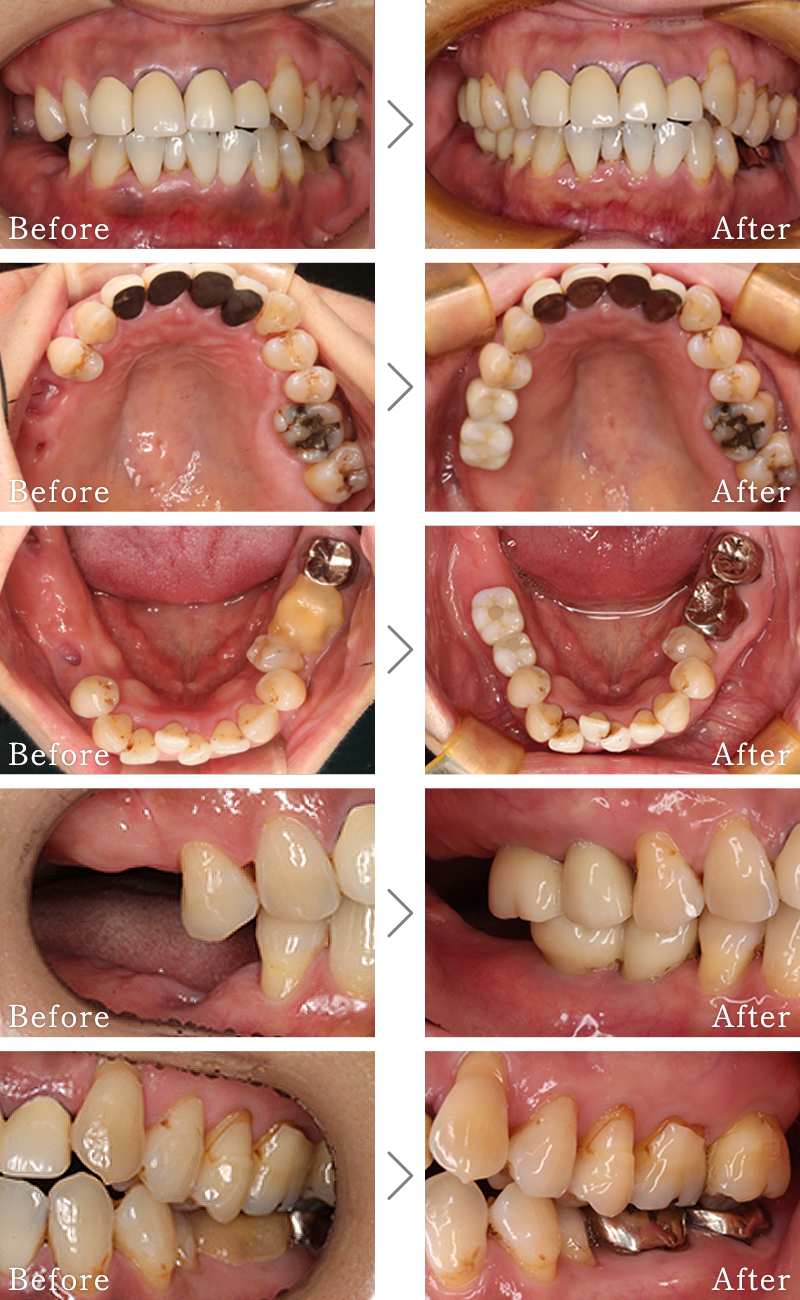

CASE2

主訴 奥歯でしっかりと噛むことができない、入れ歯もすぐに壊れてしまうとのことで来院されました。

治療法 下の奥歯を右1本、左2本のインプラントとセラミックの被せ物で噛み合わせを回復しています。

治療期間 4ヶ月

費用 CT:16,500円(税込)

+ インプラント治療:1,577,400円(税込)

合計:1,593,900円(税込)

CASE3

主訴 歯の本数が少なく、全体的に隙間があいている。

治療法 矯正治療後に上にインプラント2本使い、噛み合わせと見た目を回復しています。インプラント部位は骨が薄かったため、造骨処置(GBR)と歯肉移植(CTG)を行なっています

治療期間 10ヶ月

※矯正治療の期間は含まれておりません。

+ インプラント治療:1,051,600円(税込)

+ 造骨処置(GBR):176,000円(税込)

合計:1,244,100円(税込)

※矯正治療費は含まれておりません。

CASE4

主訴 右の奥歯は無くなって食事が噛めない。

治療法 上下2本ずつインプラントを使用して噛み合わせを回復させています。

+ 静脈内鎮静法:77,000円(税込)

+ インプラント治療:2,103,200円(税込)

合計:2,196,700円(税込)